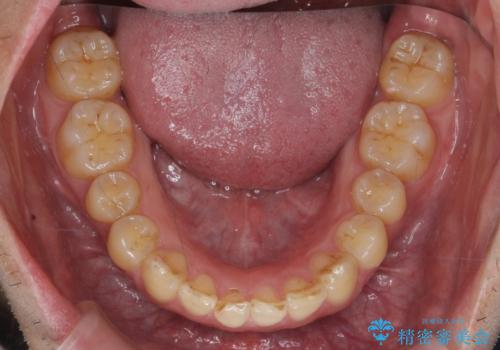

下顎は歯列を拡大して並べました。

矯正前に下顎の骨隆起の切除をご希望により行っています。(Dr.大元執刀)